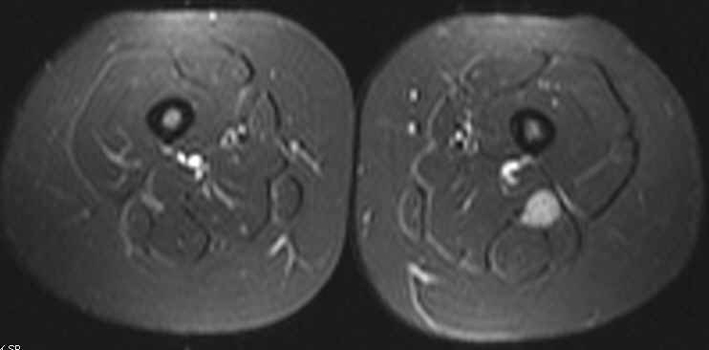

In June 2011, a surveillance PET/CT scan revealed a tubular-shaped density within the left thigh (Fig. 1). MRI evaluation of the mass demonstrated a spindle-shaped structure involving the sciatic nerve (Fig. 2). Around the same time, the patient began to experience symptoms of burning sensations and numbness and tingling in the toes of her left foot and left lower leg paresthesias in the region of the common peroneal nerve after prolonged sitting. Her physical exam demonstrated a positive straight leg raise test on the left with exacerbation of her symptoms. An ultrasound-guided biopsy was performed, revealing DLBCL cells with infiltration of the sciatic nerve. The perineurium, the endoneurim and the nerve fibers were identified; between them were large lymphoid cells that looked identical to the original lymphoma cells. An immunohistochemical stain showed that all of these large cells were CD20 positive. The histology and immunohistochemical staining were diagnostic of lymphoma of the sciatic nerve.

![]() Click for large image | Figure 2. T2-weighted image showing enlargement of the sciatic nerve when compared to the other side. |